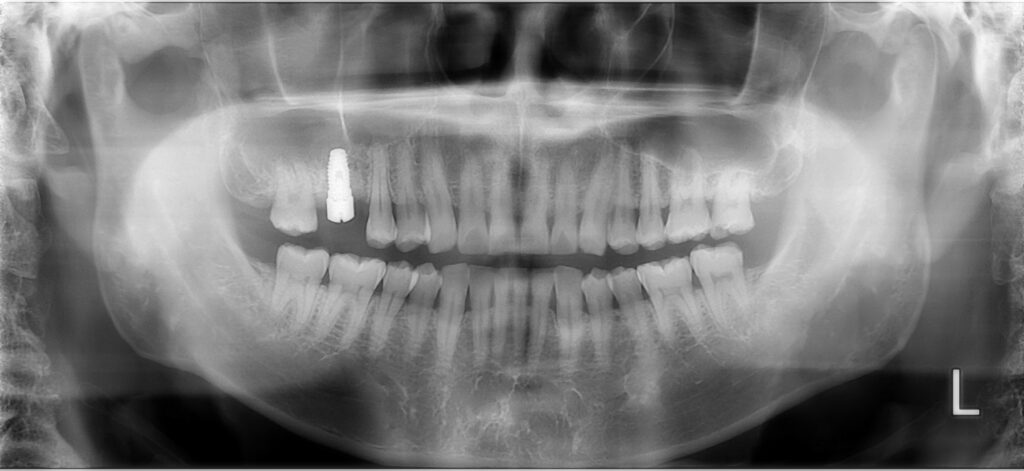

私は即座に抜歯を決断し、その後インプラントを入れました。